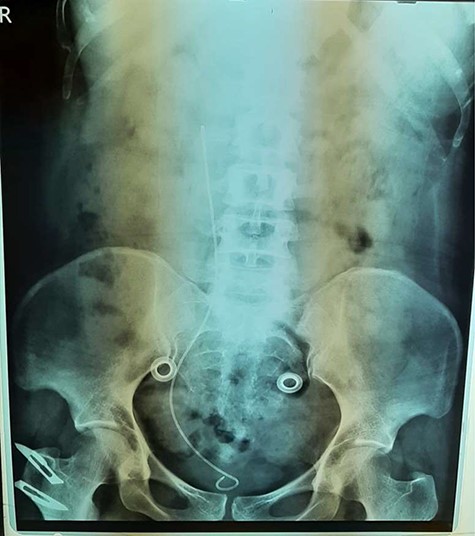

An abdominal ultrasonography revealed moderate right renal hydronephrosis and proximal hydroureter. A routine X-ray kidney-ureter-bladder (KUB) was normal. Intravenous urography (IVU) showed right renal hydronephrosis with delayed excretion and drainage (grade II) with s shape of the upper segment of the right ureter (Fig. 1). Then, the patient underwent right retrograde ureteroscopy with contrast to confirm the findings. Depending on these results, we decided to do the surgery for a right retrocaval ureter. After taking the patient consent, we had used Kocher approach to reach retroperitoneal space. After isolating of the right renal pelvis and ureter, the segment of retrocaval ureter was lower the ureteropelvic junction ~3 cm and dilated. We transected the pathological segment (~3 cm) of the ureter and then we did ureteropelvic end-to-end anastomosis. We inserted a double-j stent (Fig. 2). After a month, there was no hydronephrosis, and we removed the double-j stent. Six months follow-up demonstrates complete resolution of this pathology.

Surgery is required in symptomatic patients or in those with worsening kidney function. The standard repair of retrocaval ureter is open surgical pyelopyelostomy [3]. Repair usually involves open or laparoscopic resection of the redundant retrocaval ureteral segment, anteposition and ureteroureteral or ureteropelvic anastomosis [4]. Here we did an open surgery. After putting the patient in right flank position, the right ureter was separated first. We found the construction in level L2 and L3. We cut the constructed segment and anastomed both endings after inserting a double-j stent. Following up the patient by ultrasound is the most important part in the treatment.